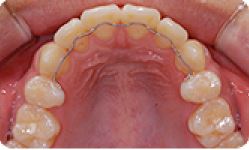

치아교정 설측브라켓 전후사례 | 2020.03.06 |